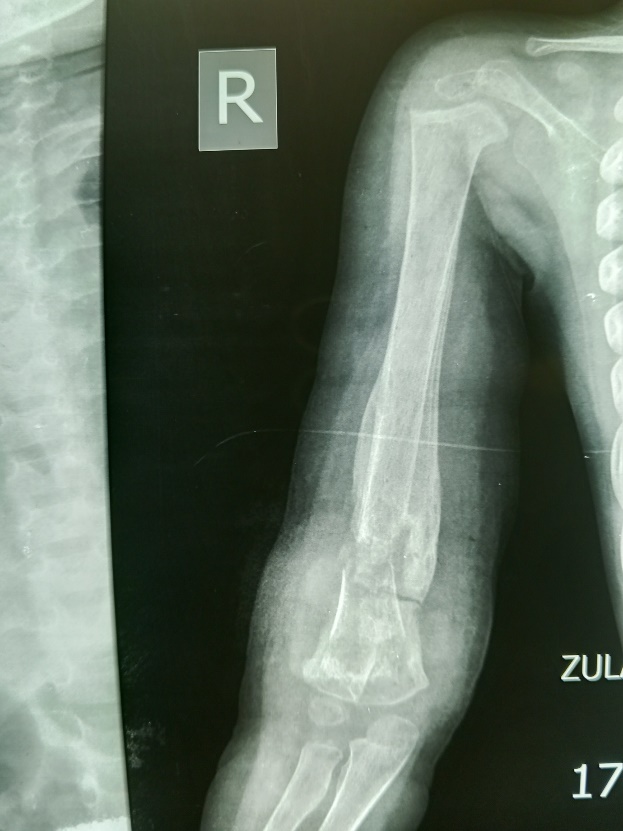

The plain radiograph demonstrated minimally displaced and complete fracture of the distal metadiaphysis of the right humerus with associated mixed sclerotic and lytic foci, areas of medullary sclerosis and lucency more on the fractured segment, with extensive periosteal reactions having triangular appearance on both cortices; the characteristic Codman’s triangle were noted. The presence of the periosteal reactions bilateral also presented the so-called bone-in-bone appearance of chronic osteomyelitis. The lucent foci in the medullary cavity of the humerus are the cloaca. There is associated marked soft tissue swelling more at the affected area with marginal irregularities especially postero-laterally; the discharging sinus. There is a suggestion of dislocation of the elbow joint but with preservation of the shoulder joint (figures 1&2).

Figure 2: Plain radiograph demonstrating the Codman Triangle periosteal reaction attached to the cortices, multiple cloacae, bone-in-bone appearance, dislocation of the right elbow joint, marked soft tissue swelling with marginal irregularities.